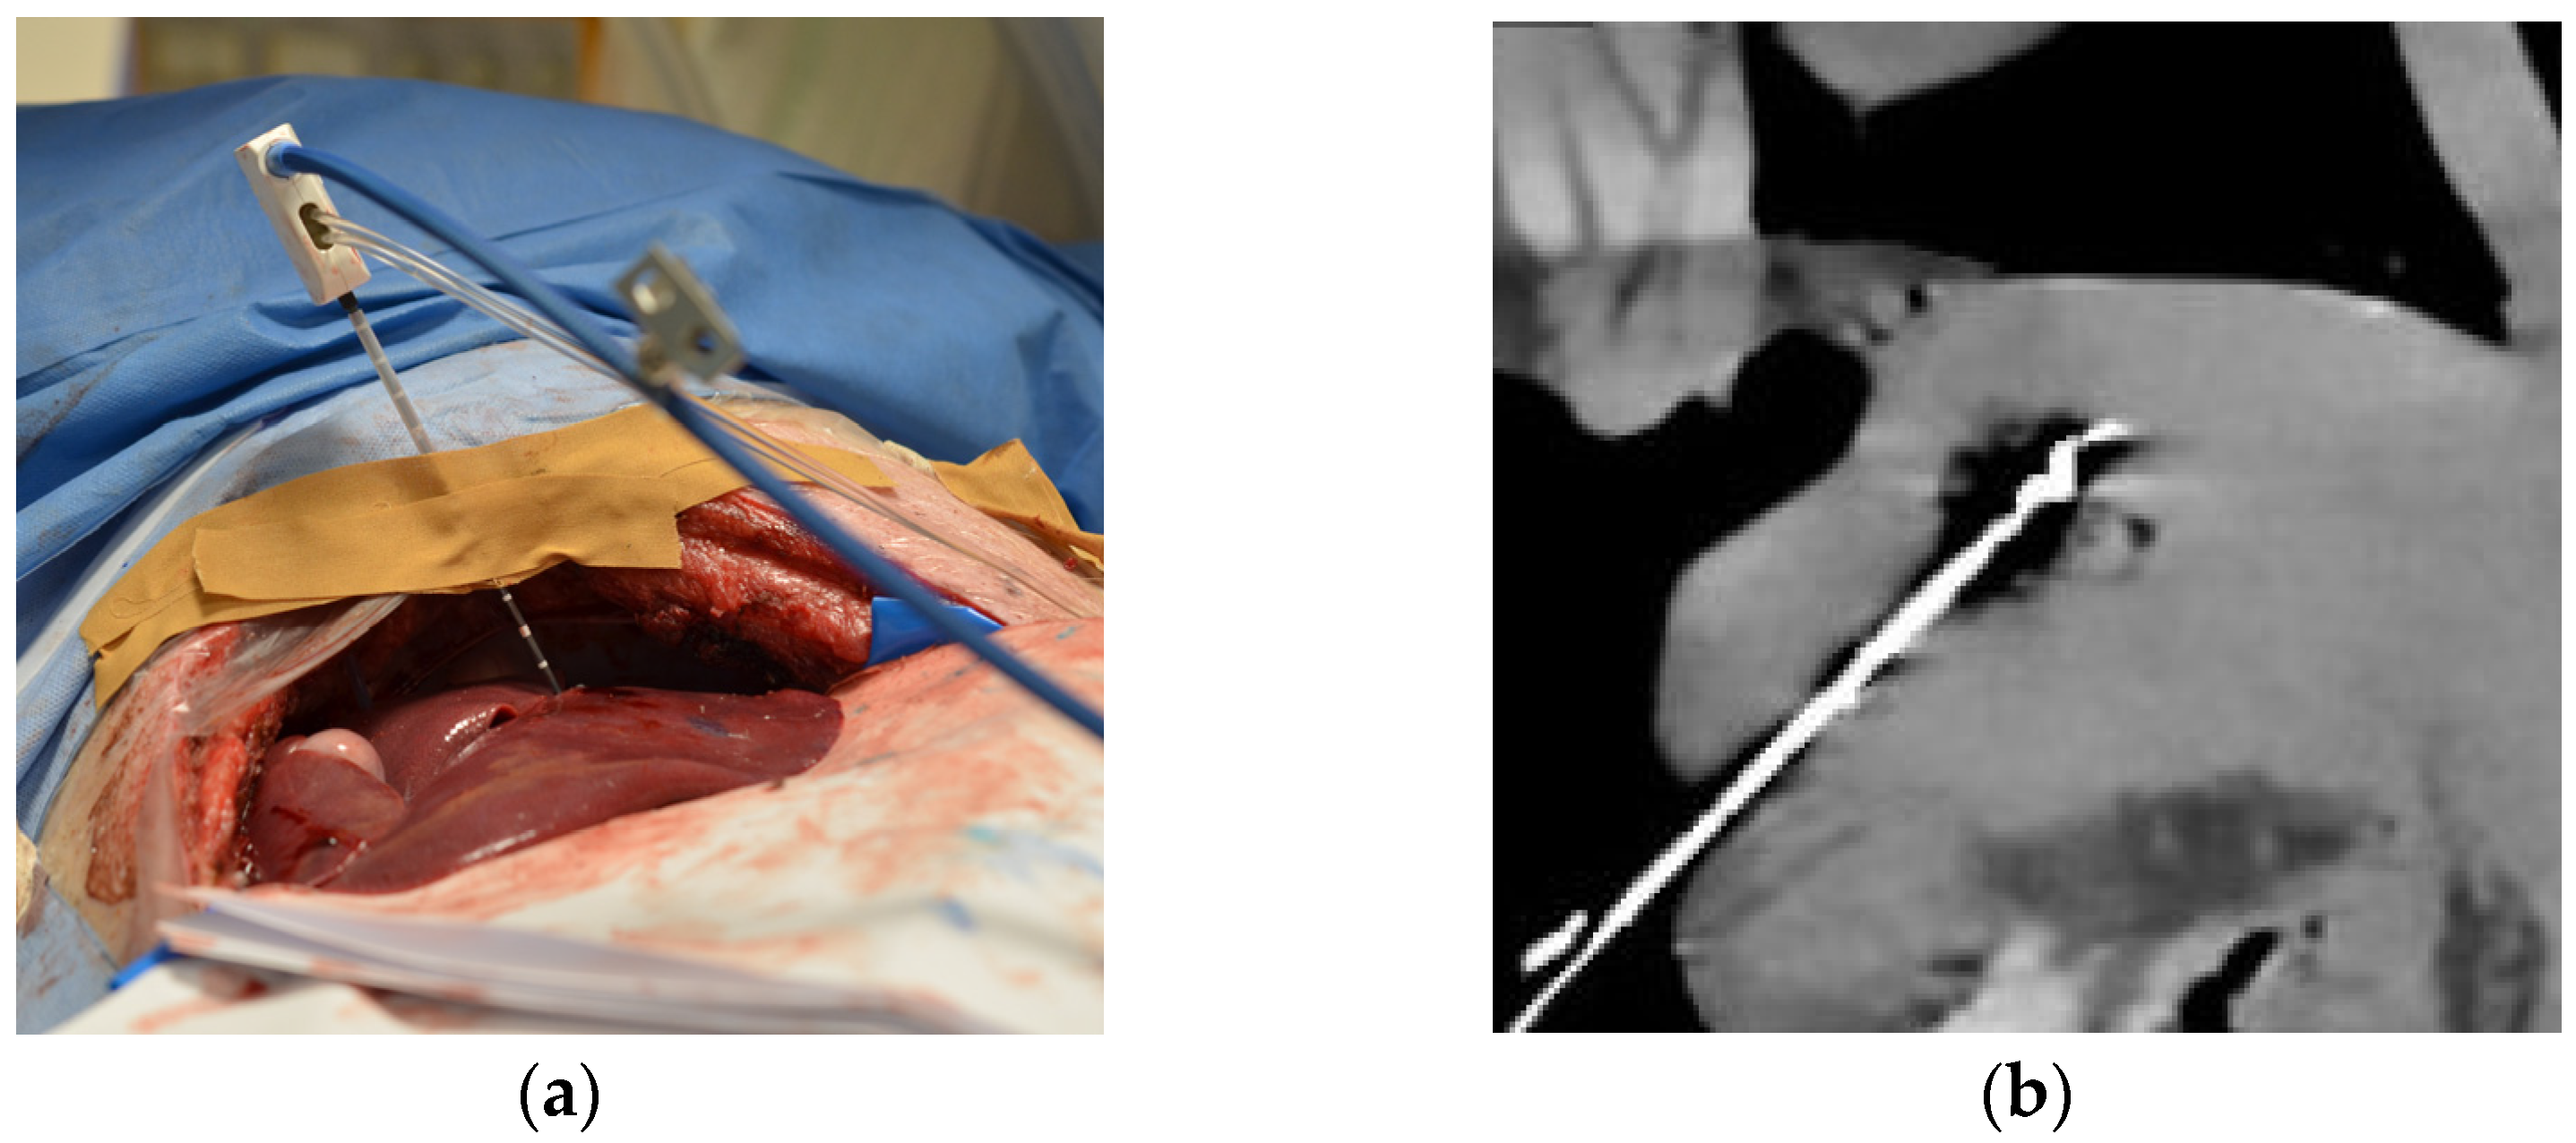

2.1. Experimental Setup and Protocol